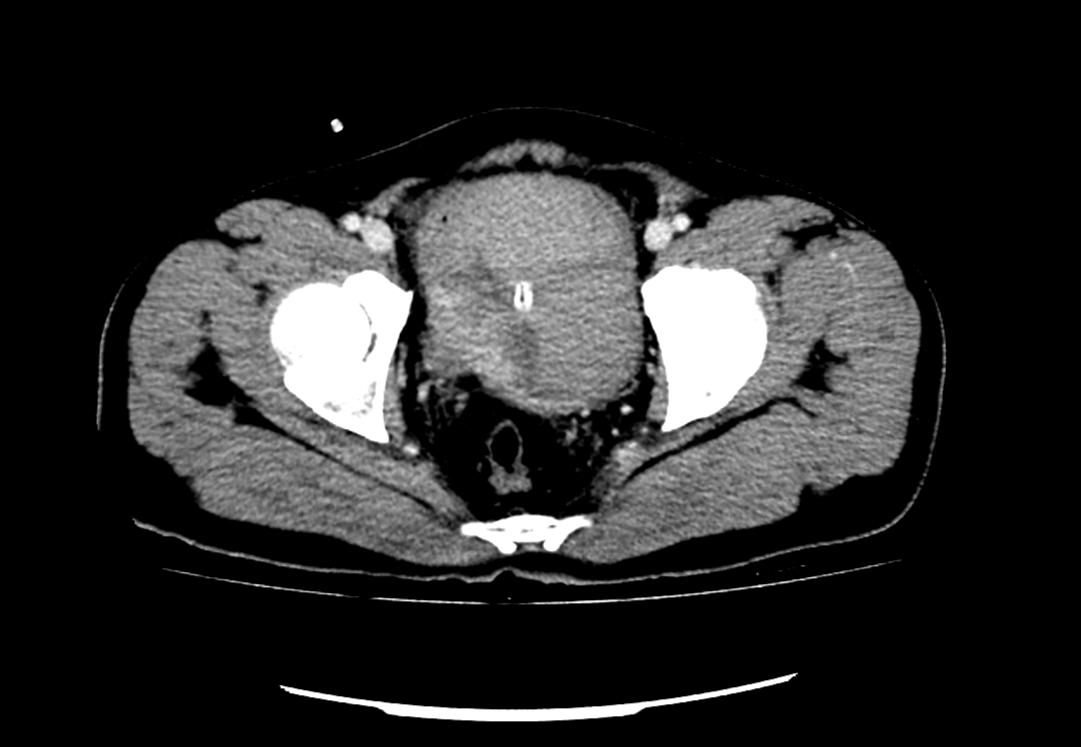

患者為53歲的男性,患者因肉眼血尿就診我院門診,行泌尿系CT考慮膀胱占位,建議患者住院治療,入院后完善膀胱MRI檢查進(jìn)一步診斷膀胱腫瘤,侵犯肌層。行膀胱腫物激光切除后,病理學(xué)檢查明確“膀胱高級別尿路上皮癌,肌層浸潤”診斷,結(jié)合泌尿外科診療指南建議行根治性膀胱全切術(shù)。

泌尿外科醫(yī)生團(tuán)隊術(shù)前將患者情況上報醫(yī)務(wù)科,并組織了多次會診?;颊?/span>“肌層浸潤性膀胱癌”診斷明確,術(shù)前完善心肺功能排除無明顯手術(shù)禁忌,結(jié)合指南推薦及泌尿外科團(tuán)隊成員綜合意見,決定在全麻下行腹腔鏡下膀胱根治性切除+盆腔淋巴節(jié)清掃+回腸代膀胱手術(shù)。術(shù)前嚴(yán)格完善準(zhǔn)備工作,手術(shù)歷經(jīng)7小時,完整切除了患者的膀胱、前列腺及精囊,并行回腸代膀胱。手術(shù)順利,術(shù)后3天可正常行走,復(fù)查患者各項指標(biāo)正常。